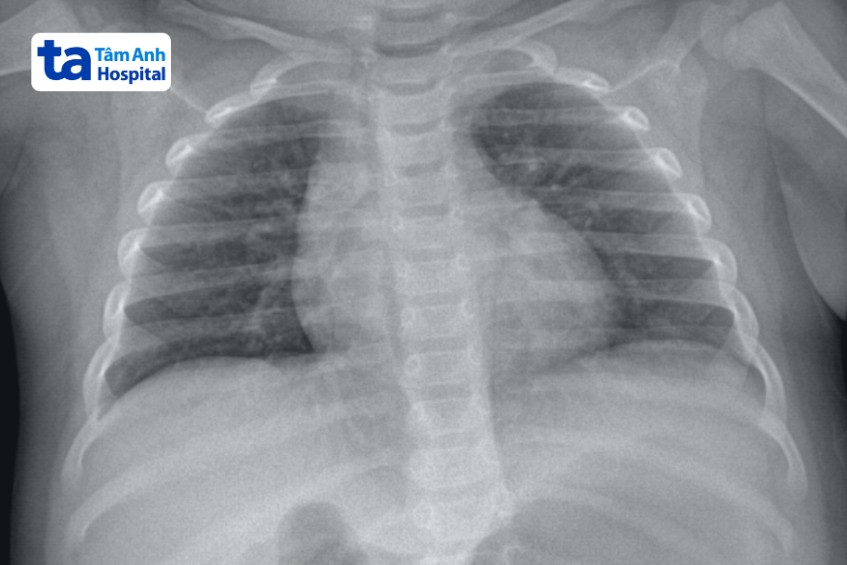

Chụp X quang là phương pháp tạo nên hình ảnh giải phẫu cấu trúc cơ thể một cách khá chi tiết bằng cách sử dụng tia bức xạ X. Đây là loại tia có khả năng đi xuyên qua và được các cơ quan trong cơ thể hấp thụ với mức độ khác nhau.

Dựa vào phim X quang, bác sĩ có thể quan sát, đánh giá về bộ phận cơ thể cần kiểm tra, chẩn đoán chính xác về sự tổn thương do chấn thương hoặc bệnh lý và đưa ra hướng điều trị phù hợp.

Bác sĩ có thể chỉ định trẻ em thực hiện chụp X quang trong các trường hợp sau đây: